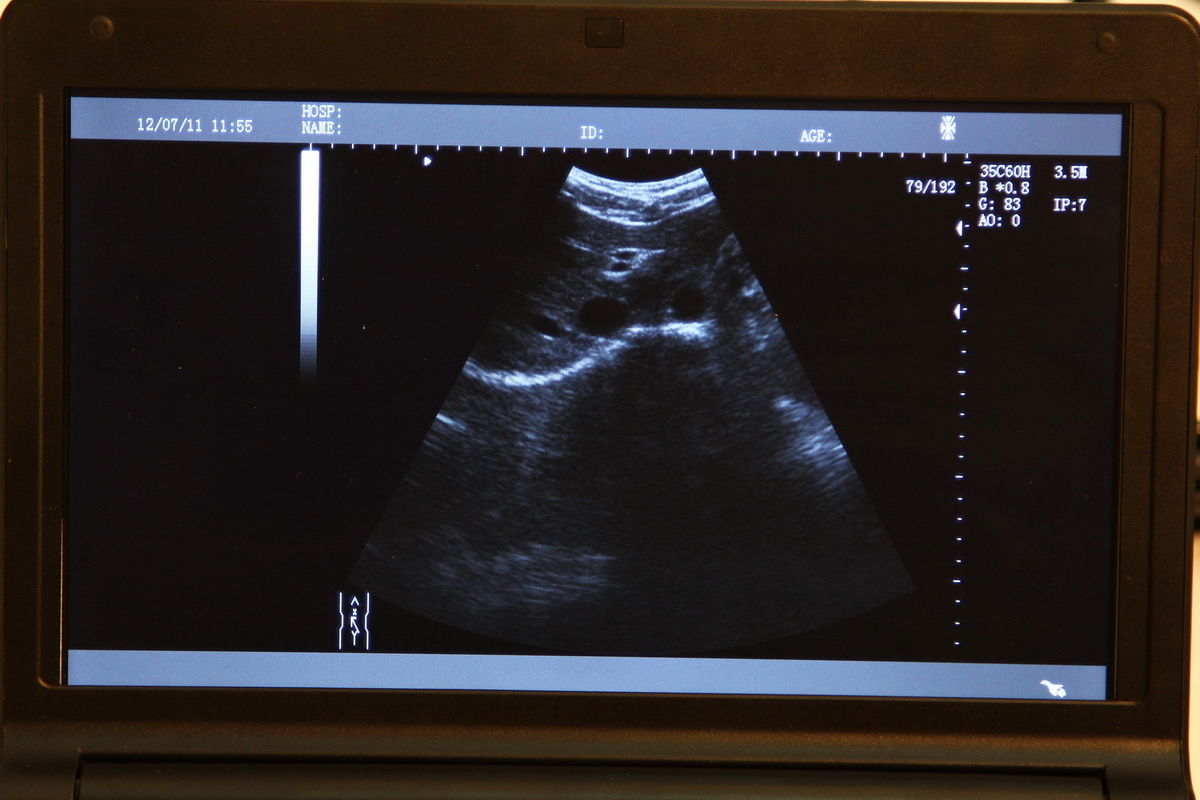

The CE Digital Laptop Ultrasound Machine offers outstanding imaging capabilities that are essential for modern diagnostic practices. It features a 6.5MHz Transvaginal probe that provides high-resolution images, enabling healthcare professionals to visualize internal structures with great clarity. This machine is designed to help in various examinations, ensuring better accuracy and improved patient care.

The CE Digital Laptop Ultrasound Machine enhances user experience with its intuitive interface and advanced functionality. It supports 3D imaging, allowing healthcare providers to obtain more detailed views of the anatomy being examined. This capability is invaluable for procedures such as gynecological assessments, as it provides a comprehensive perspective that traditional ultrasound machines cannot offer.